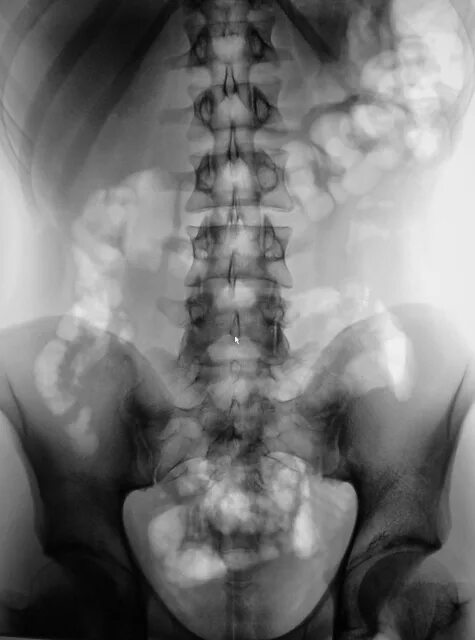

Опущение почки симптомы и последствия